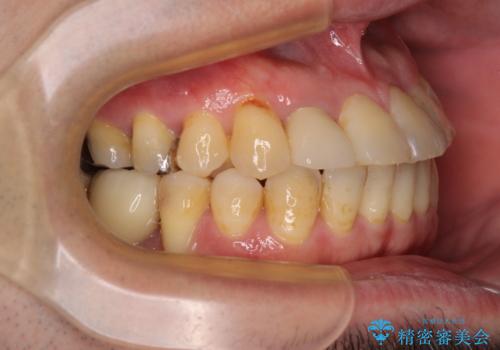

骨造成や歯肉移植など、治癒期間の長い処置を必要としたため治療期間は長くなりましたが、安定した咬み合わせと整った歯列となり、患者様には大変満足していただきました。

矯正治療でインプラント埋入を行い、矯正治療後に気になる前歯と合わせてオールセラミッククラウンによる補綴治療を行うこととしました。